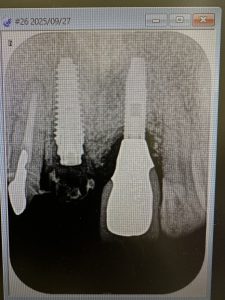

土曜日朝、前歯の抜歯即時

切歯管が近接しているから慎重にがテーマ!

その前に、部分抜歯し唇側束状骨の吸収を防ぐ!

色々な名称あり、ソケットシールドやらルートメンブレンやら他もあり